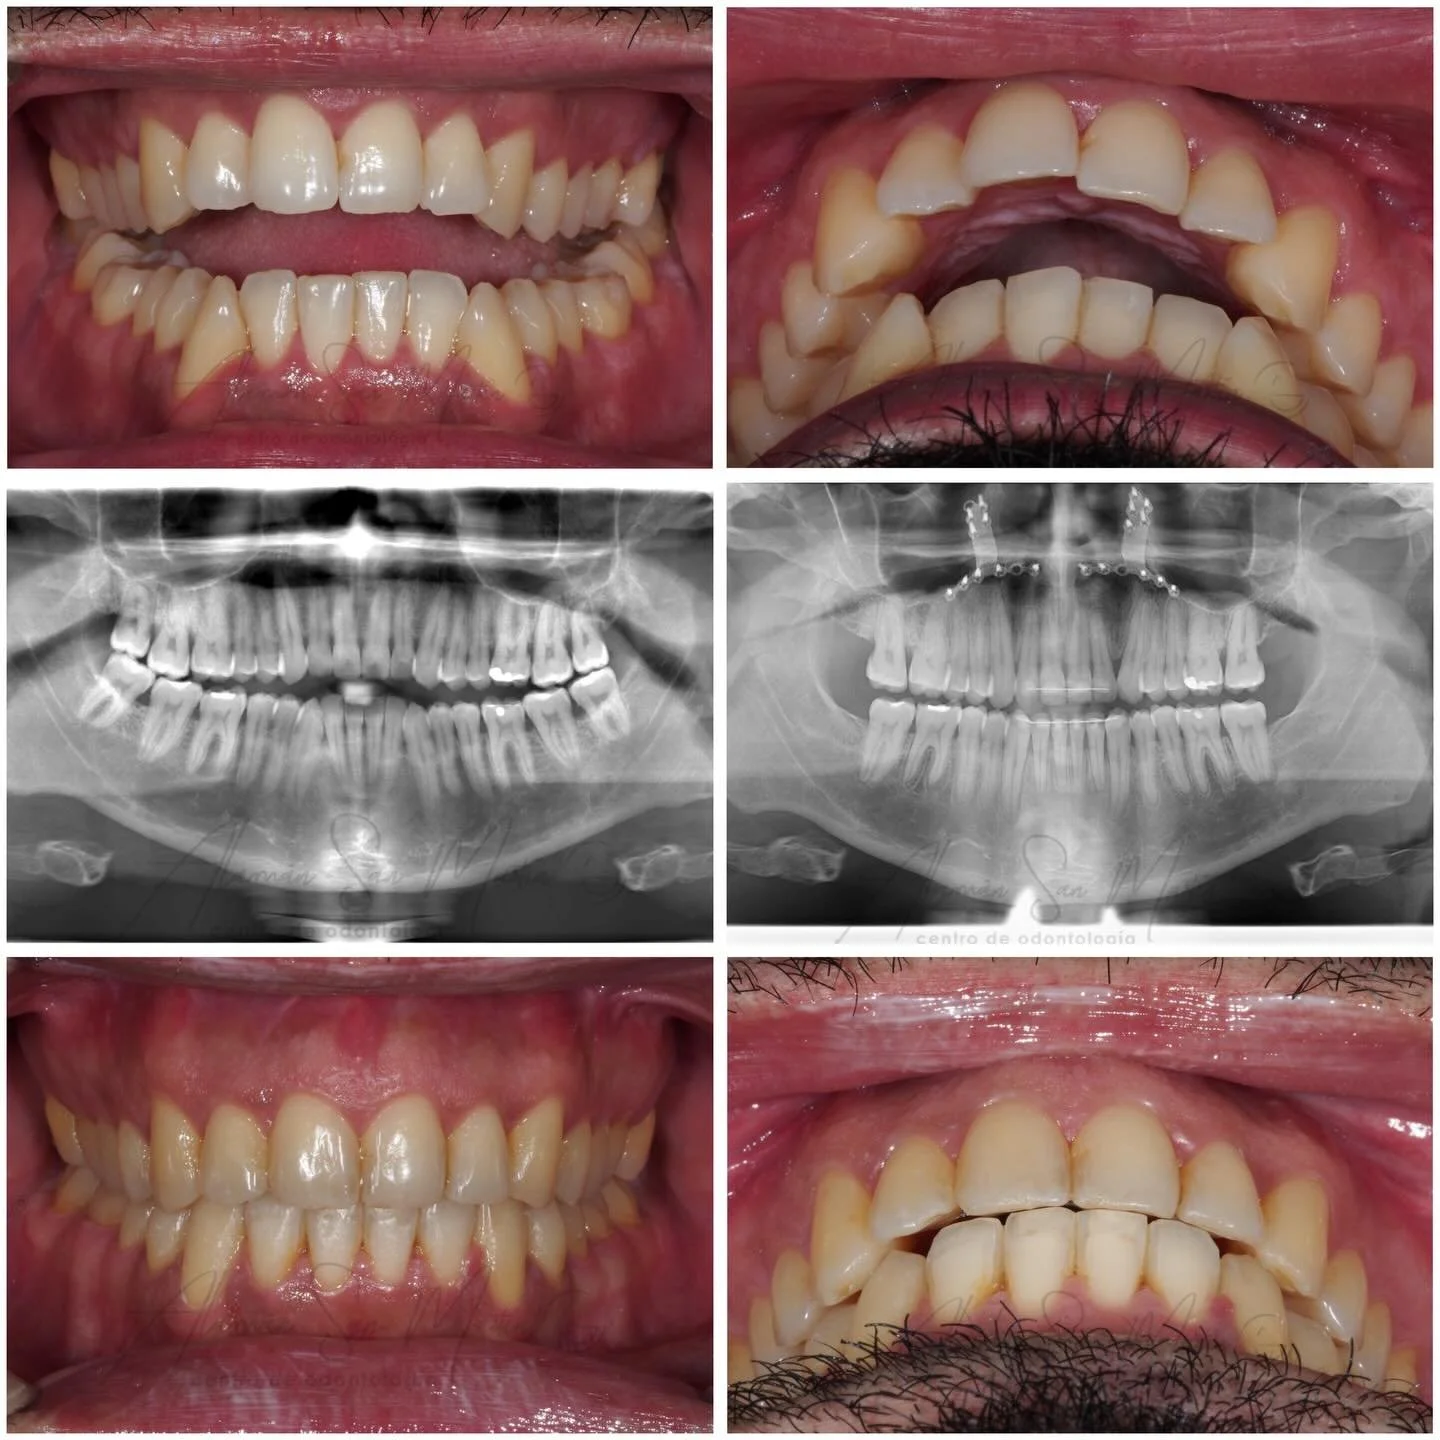

A nuestra clínica acuden muchos pacientes remitidos de los servicios de Cirugía Maxilofacial de los Hospitales de Madrid con problemas óseos y de maloclusión oseodentaria grave que requieren una preparación de ortodoncia antes de la Cirugía Ortognática en su Hospital.

En la clínica se realiza Ortodoncia Quirúrgica en adultos desde 1998, con excelentes resultados gracias al trabajo de los Cirujanos Maxilofaciales en combinación con nuestra Ortodoncia y la exacta preparación de las Férulas Quirúrgicas por nuestros protésicos.

La Ortodoncia Prequirúrgica cambia las inclinaciones de los dientes y consigue una buena forma de arcada sin apiñamiento para que haya una oclusión estable en la cirugía.

La Ortodoncia Postquirúrgica mantiene la posición ósea obtenida con la cirugía y termina de conseguir la mejor oclusión equilibrada posible en el paciente.